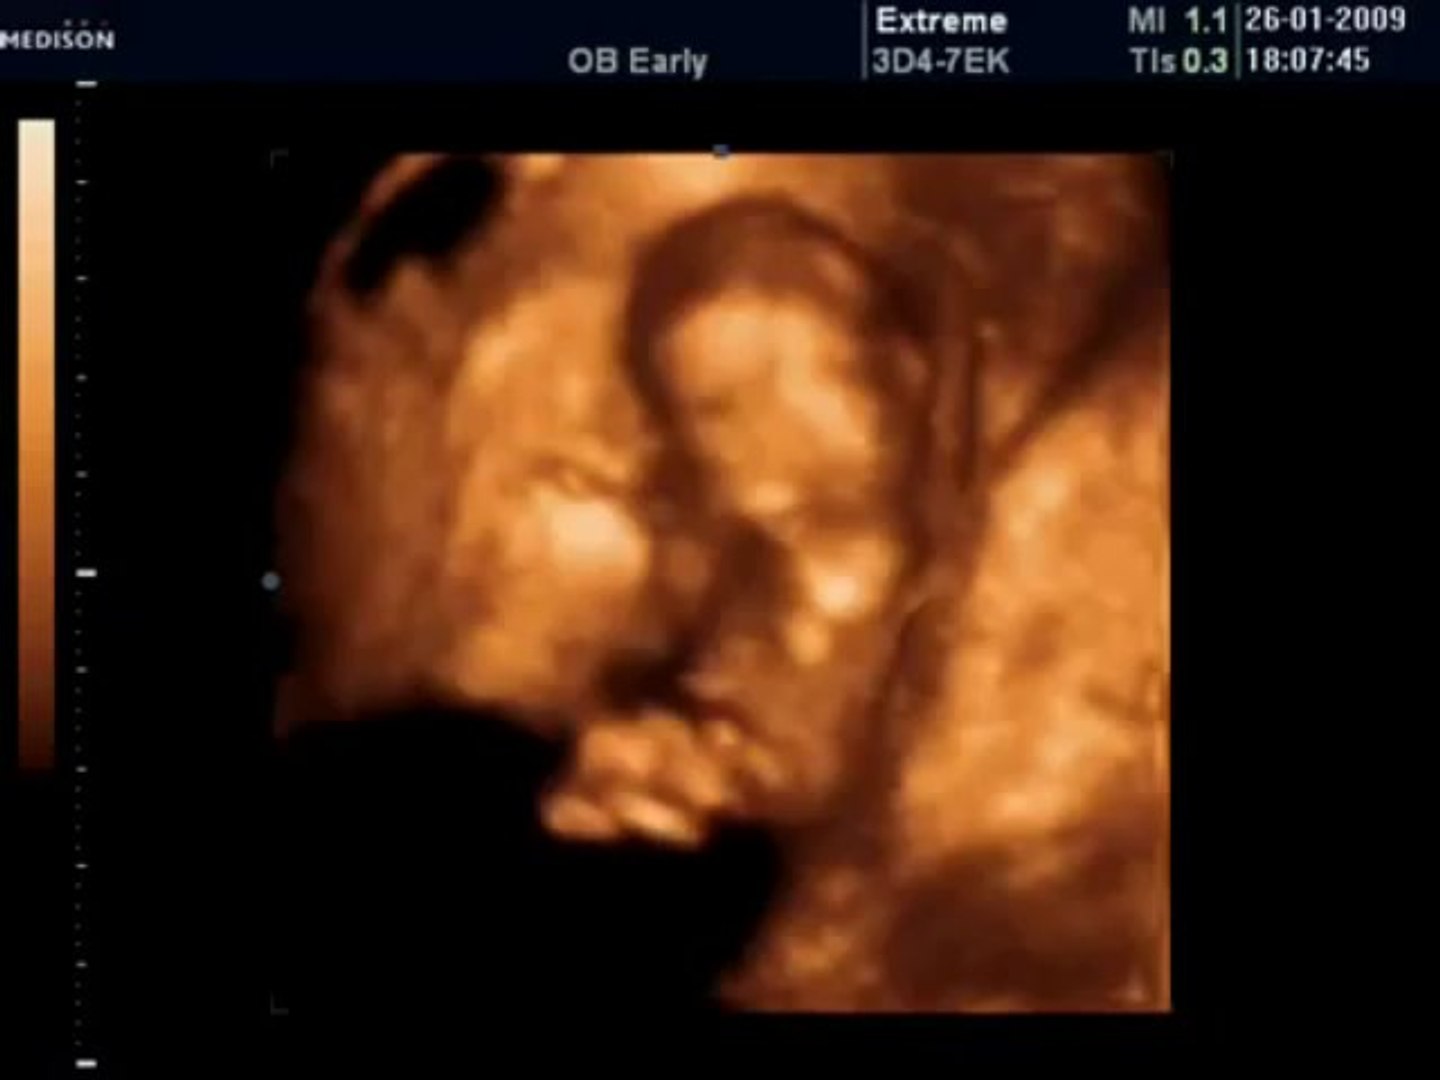

22 Haftalık Bebek Görüntüsü 4 Boyutlu

32 haftalik hamilelikte 4 boyutlu ultrason goruntusu youtube